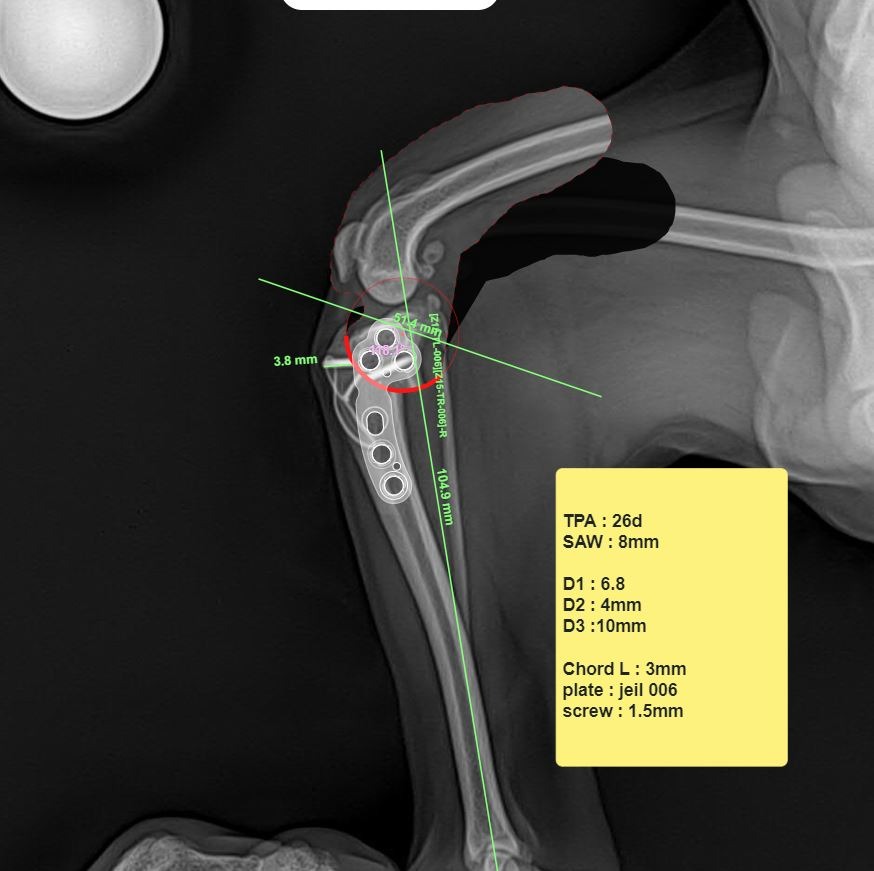

수술 전 시뮬레이터 사진 / 출처: 라온동물메디컬센터

라온동물메디컬센터에서는 TPLO 수술 전 정형외과 전용 시뮬레이션 프로그램을 활용해 경골의 각도, 절골 범위, 플레이트 고정 위치를 사전에 정확하게 계산합니다. 이 과정은 수술의 정확도는 물론, 수술 후 관절 안정성과 회복 속도를 높이는 데 중요한 역할을 합니다.